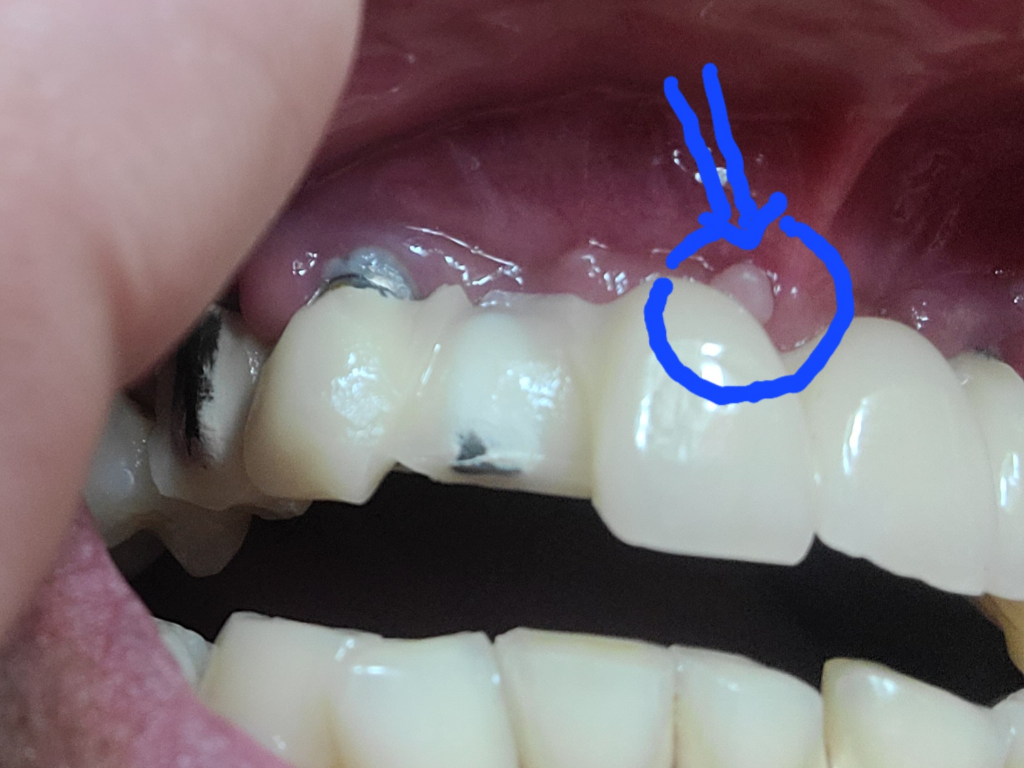

갑자기 이게 보이는데 뭐죠?겁나네요

오늘 윗입몸을 확인해보니 저기 표시된 동그란게 발견되더라구요ㅜㅜ 아요즘 정말 몸에 변화가 와서 걱정이에요ㅜㅜ

종양은 아니겠죠?ㅜㅜ

사진으로 보았을 때는 구내염인 것으로 보입니다. 구내염은 다양한 원인에 의해 나타나며 외부 자극, 스트레스 및 음식 섭취 등에 의해서도 나타날 수 있습니다. 물론 정확한 것은 치과 방문 후 검사를 해보아야겠지만 보이는 부분만 봤을 때는 구내염일 수 있어 보입니다. 해당 부위가 2주 이상 지속될때는 치과 방문 후 감별진단을 받아보셔야 합니다.

종양은 아닌거 같으며 잇몸이 증식된 것으로 보이나 보다 정확한상태한 파악을위해 빠른 시일내에 치과를 방문하여 진료를 받으시길 권장드립니다.

잇몸이 과증식되신거 같아요. 치과가셔서 사진도 찍어봐야 알겟지만, 크게 걱정할껀아니세요. 과증식이라면 그냥 마취후 제거하면됩니다.

치아뿌리쪽이 아니고 치아쪽에 가까이 생긴 고름주머니이면 잇몸염증인 경우가 많습니다.

면역력이 떨어질경우 치석이나 잇몸의 외상에 의해 고름주머니가 생길수 있습니다.

구강위생상태가 좋아지면 호전되는경우가 많습니다.

지속된다면 치과 방문해야 합니다.